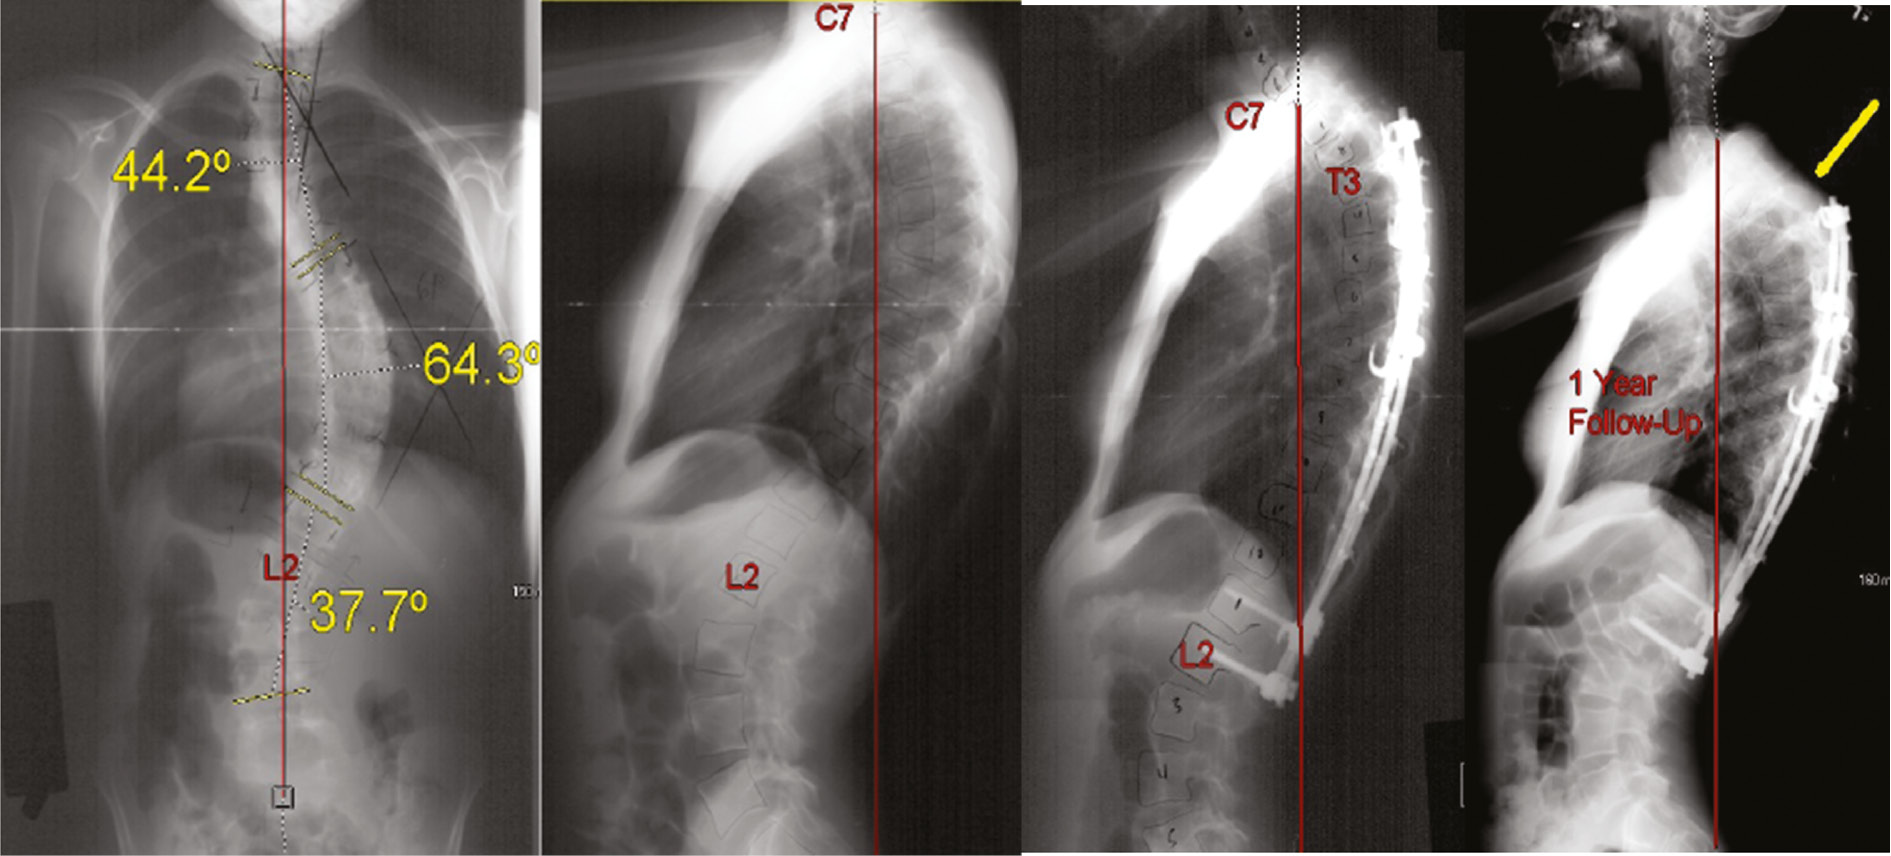

Mechanical low back pain is a diagnosis of exclusion, so making this diagnosis requires ruling out other causes of back pain, especially those associated with risk of significant complications. In the postoperative population, plain films are important to rule out other sources of pain, especially implant-related problems (Figure 1), progressive deformity, or adjacent degeneration.

Figure 1. Pedicle screw fracture with low back pain may indicate pseudarthrosis.

jposna20220030_fig1.jpg